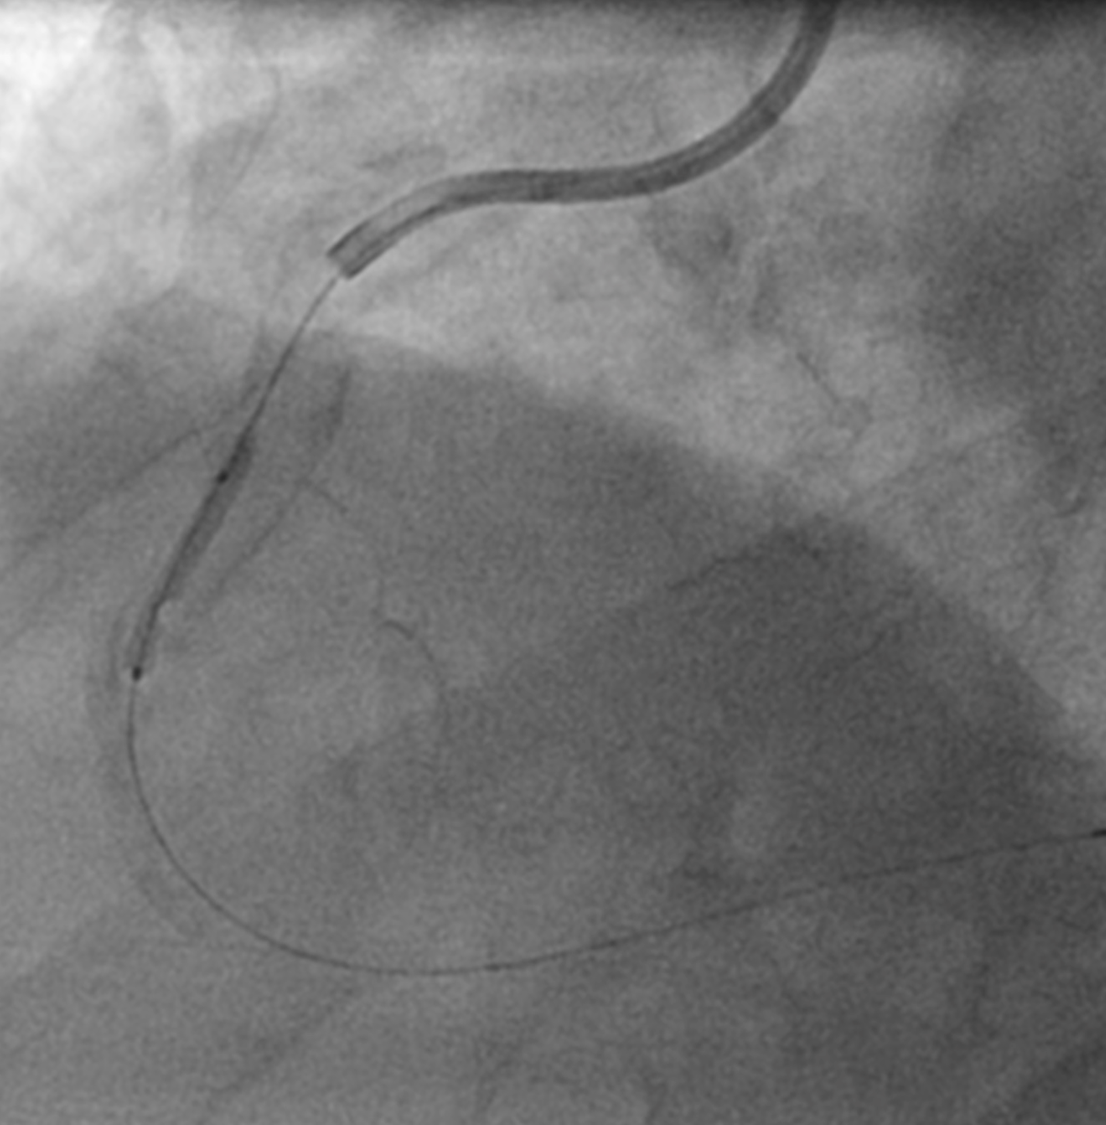

A 79-year old male with hypertension and moderate left ventricular impairment was admitted to hospital with a non-ST segment elevation myocardial infarction (NSTEMI). A diagnostic angiogram showed severe right coronary disease with moderate disease in the left coronary system (Figure 1a - 1c). The patient was transferred to our tertiary centre for complex percutaneous coronary intervention (PCI) to the culprit right coronary artery (RCA) with calcium modification and intravascular imaging (IVI).

There was a mild troponin elevation of 52 ng/mL. Diagnostic angiography showed moderate disease in the left coronary system (Figure 1a & 1b). A Heart Team discussion was undertaken with a decision to perform PCI to the severe culprit RCA lesion (Figure 1c) using calcium modification and IVI, with a right radial artery approach and a 7F AL 1.0 guide catheter.